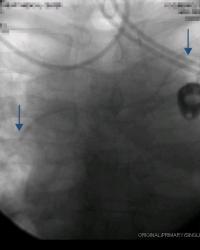

Figure - 06

Example of how S.V.C. can be very long in some patients. Right-sided V.A.D. contrast injection. |